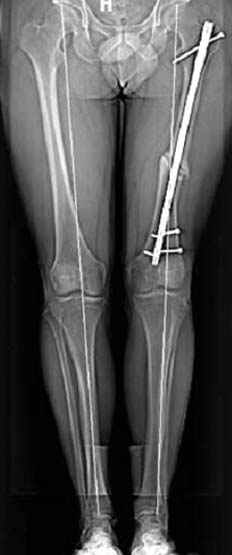

Несколько снимков из моей коллекции, чтобы разьяснить, почему мы до сих пор делаем различные варианты остеотомии.

На рисунке N1 предоперационный план лечения ложного сустава шейки бедра- линия ложного сустава, угол и направление введения импланта, клиновидная остеотомия в градусах и миллиметрах, второй снимок после коррекции, расчет, на сколько удлиняется конечность и размеры импланта;

N3 рисунок окончательный снимок, после операции моя рентгенограмма должен выглядеть примерно как эта картина. На N4 снимке клин перед удалением; N5 послеоперации 3 нед.; N6 окончательная рентгенограмма.

Djoldas Kuldjanov 23 Ноябрь 2004, 18:21

пластическая модель; и коррекция бедра аппаратом Илизарова.